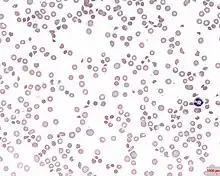

| A photomicrograph of the blood showing thrombocytopenia | |